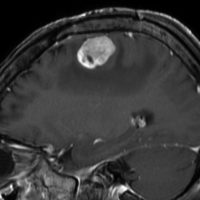

第4脳室床に発生した典型的な上衣腫 EPN-PFA の画像です。水頭症になって,頭痛と嘔吐,意識障害で発症しました。典型的なMRI画像と病理所見です。MRIでは第4脳室からマジャンディー孔を越えて脊髄背側まで長く腫瘍が伸びています。腫瘍内部に小さなのう胞が複数みられます。病理像では,血管周囲に細胞核がない無核野が認められます。血管周囲に伸びた繊細な単極性突起が集まった領域です。これは,血管周囲偽ロゼット perivascular pseudorosette という上衣腫に特徴的な病理所見です。

幼児の巨大な上衣腫です。左ルシュカ孔から延髄を取り囲む様に小脳延髄角槽に進展しています。最も典型的で治療が難しいタイプです。これはT2強調画像ですが,ガドリニウム増強されないものでした。

左が術前,右が術後です。脳底動脈の周囲が摘出できませんでした。幼児ですが手術後には局所照射をするしか方法がありません。